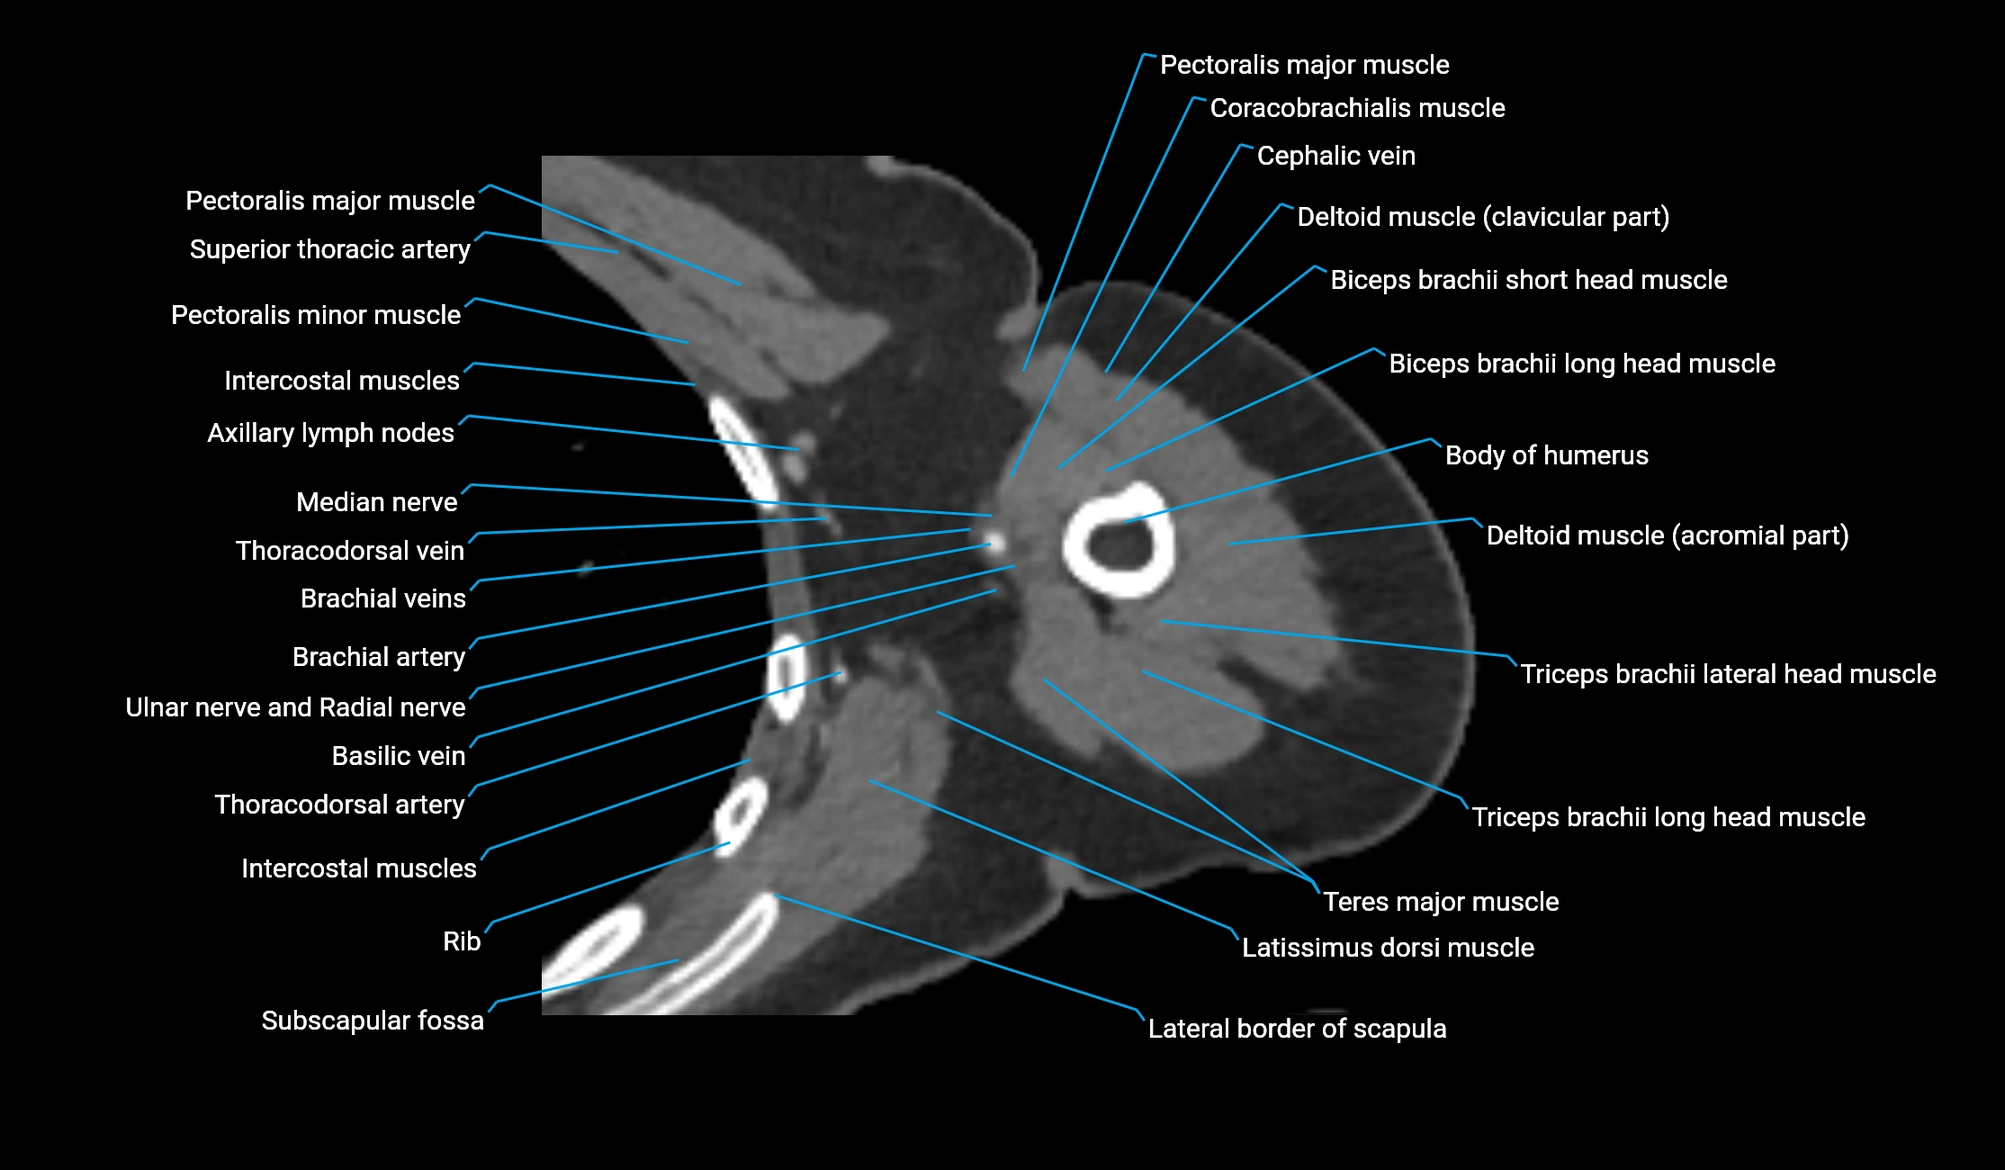

CT image